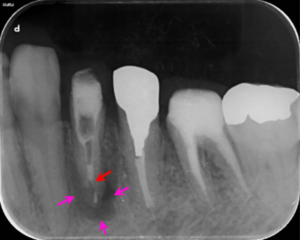

左下6番の歯の根管治療終了3か月後に、左下4番の歯の根管治療を開始した後のレントゲン写真です。以前に根に詰めてあった薬を除去している途中です(矢印赤)。まだ根の先の骨の溶けている部分の大きさは変わりません(矢印ピンク)。